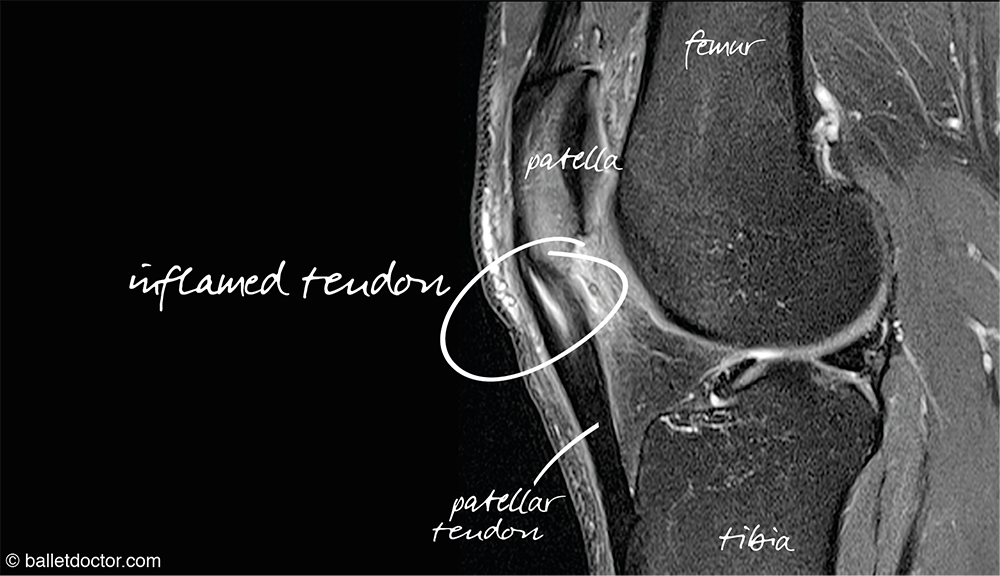

Chronic pain is a very common problem in repetitive load based sports which if you were to choose a phrase to describe powerlifting I think you would be hard-pressed to find a better one. One of the most common forms of pain is a tendinopathy specifically in the knee patella tendinopathy is very common. Before we continue we will briefly discuss what a tendinopathy is

Tendinopathy refers to a disease of a tendon. The clinical presentation includes tenderness on palpation and pain, often when exercising or with movement.[1]

Once you have developed a tendinopathy such as patella tendonitis which is an incredibly common affliction in running jumping athletes (it is also known as jumper’s knee) and the most common knee flare up I have seen in lifters then you need to begin a management strategy.